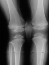

This patient is an 11 year old white male with a diagnosis of Multiple Epiphyseal Dysplasia (MED). Initially he presented with x-rays revealing mild genu valgum which progressed such that he required surgery. He had supracodylar osteotomy which was performed in 1993 for genu valgum . He was last seen in August 1995 for low back pain for which he was prescribed stretching exercises. Since the last visit he has had no problems with his back and denies any complaints in his lower extremities, with the knee valgus remaining stable .

Examination revealed a significantly obese boy in no acute distress. Examination of his back showed no evidence of any curvature. There was no tenderness of his entire spine. Examination of his legs revealed bilateral genu valgum with an intermalleolar distance of 13.5 cm. There was no evidence of any knee effusion or tenderness of the knees. Neurovascular status of the lower extremities was normal with 5/5 muscle tone bilaterally.

In radiograms, the principal findings are the delay and irregularity of ossification of the epiphyses, which are markedly fragmented and mottled. They appear flattened.